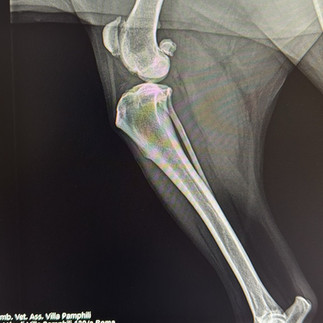

Siamo lieti di presentare alla nostra clientela la nuova Radiologia Digitale Diretta ad alta definizione, in grado di offrire ai nostri pazienti una diagnostica per immagini ancora più affidabile e sicura, soluzione che bypassa le limitazioni delle tecnologie precedenti. La nuova radiologia digitale rappresenta un avanzamento significativo rispetto al passato consentendo una diagnosi più rapida e precisa.

Le immagini vengono acquisite, visualizzate e archiviate in formato elettronico in modo da permettere una gestione più efficiente dei dati migliorando così la cura dei nostri animali.